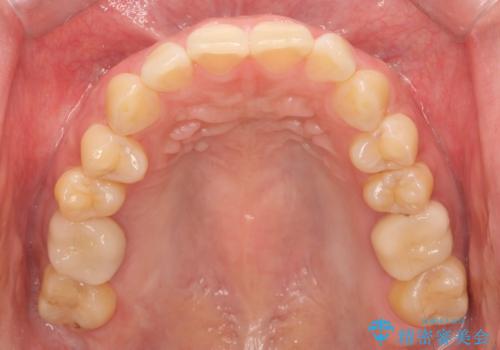

- 夜間の歯ぎしりを指摘されたことでナイトガード作成を希望して来院された患者様です。

厚いナイトガードでかみ合わせを微調整していきます。

全ての歯が均等に噛み合うよう調整することで噛む力を分散させ、一本の歯に噛む力が集中しないようにします。